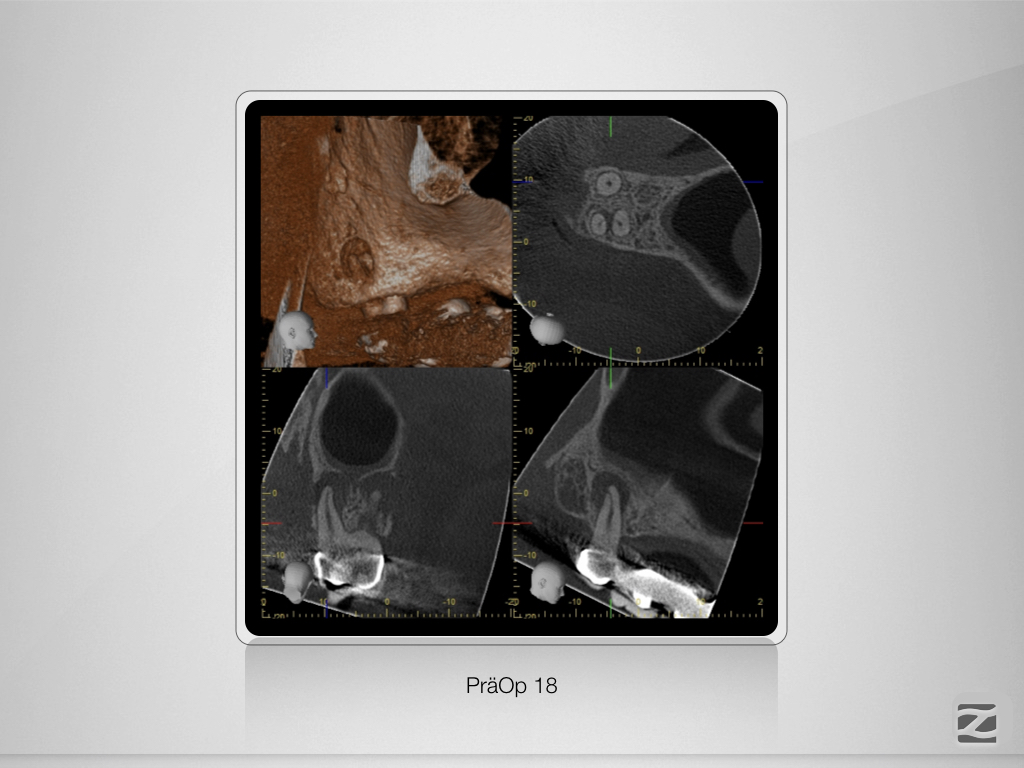

18D.001

Erfreuliches Recall